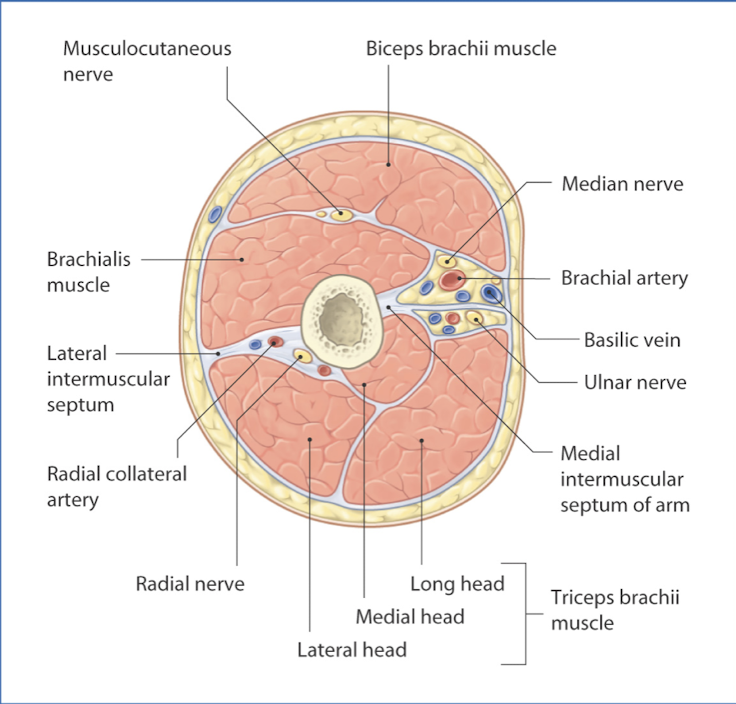

Extremity layers

• Skin (epidermis/dermis)

• Superficial fascia

• Adipose

• Deep fascia

• Epimysium covers muscle

• Periosteum covers bone

• Neurovascular bundles

• Compartments (anterior and posterior)